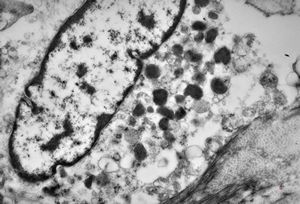

M, 62y. | Weibel-Palade body - angiomatous tumor, v.s. Kaposi sarcoma